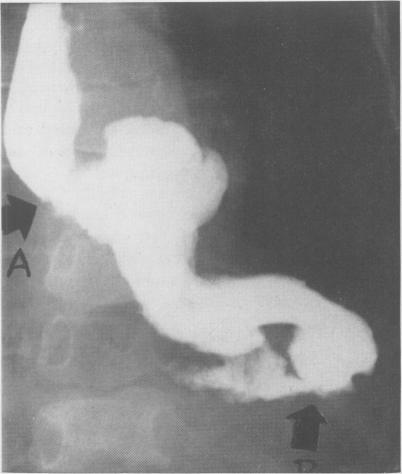

Colonic replacement of distal esophagus and proximal stomach in the management of bleeding varices in children.

Ann Surg. 1958 Jan;147(1):17-25. doi: 10.1097/00000658-195801000-00003.